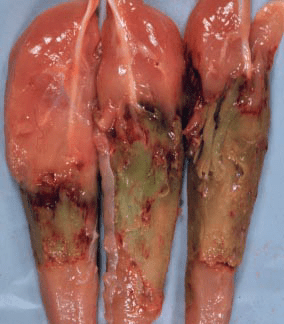

Category 3: This stage reveals the progressive degeneration and greening of the damaged tissue (see Figure 4). Often, only the middle part of the fillet is involved and the progressive greening is in parallel with the loss of cellular structure, so that a ‘putty like’ consistency develops within the lesion. This green, necrotic area will persist and through time will gradually reduce in size as it is reabsorbed so that the sym metry of the breast is lost in some older birds. The green color is produced by the breakdown of hemoglobin and my oglobin to bile salts.

Figure 4: Aged Pectoral Myopathy